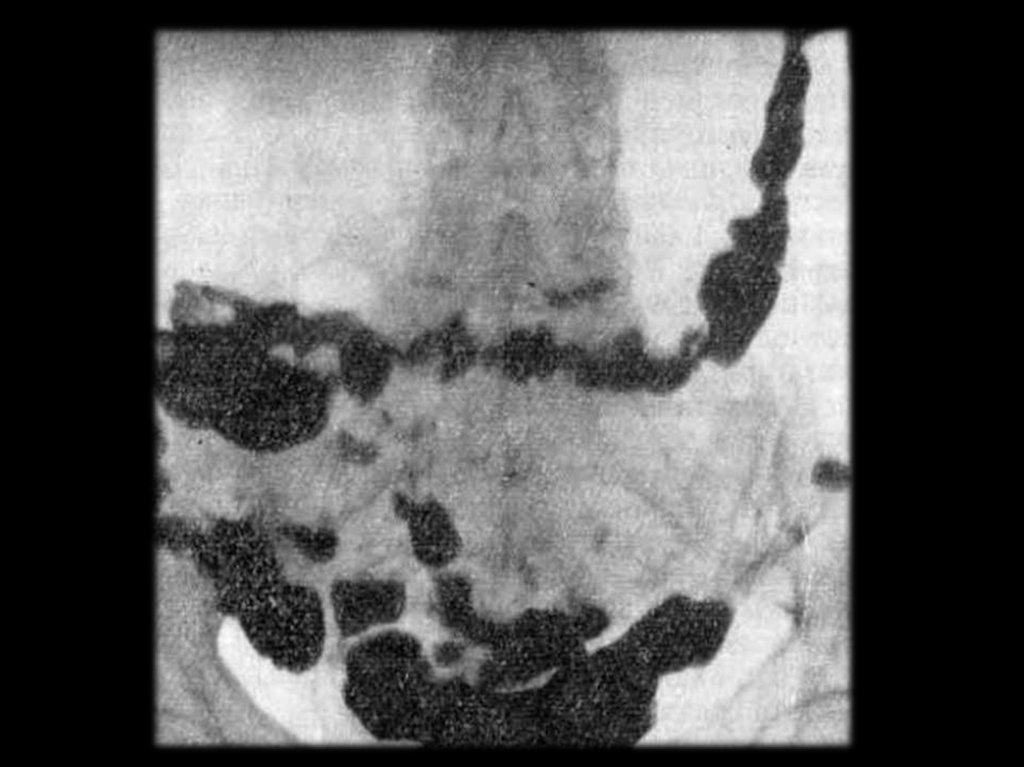

Желудочно-кишечный тракт – 70%.

Пищевод – дисфагия, отрыжка, срыгивание,

Кишечник – запоры, нарушение всасывания

изжога, зияние розетки кардии.

– спруподобный синдром.